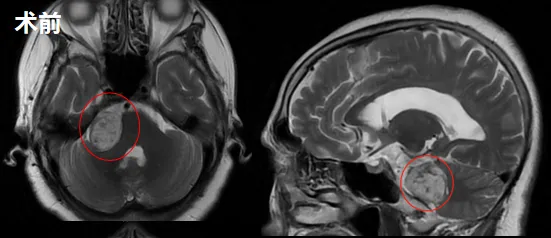

家人这才慌了,带她去当地医院检查,在2021年5月、10月两次MRI检查后最终确诊:右侧听神经瘤(大小20mm×15mm×19mm),还合并了脑积水。

就在家人权衡决策时,2022年10月的常规检查带来了紧迫感:肿瘤已增大至32mm×22mm×26mm,超过了3厘米!对于这样的大型肿瘤,手术切除已成为必然选择。